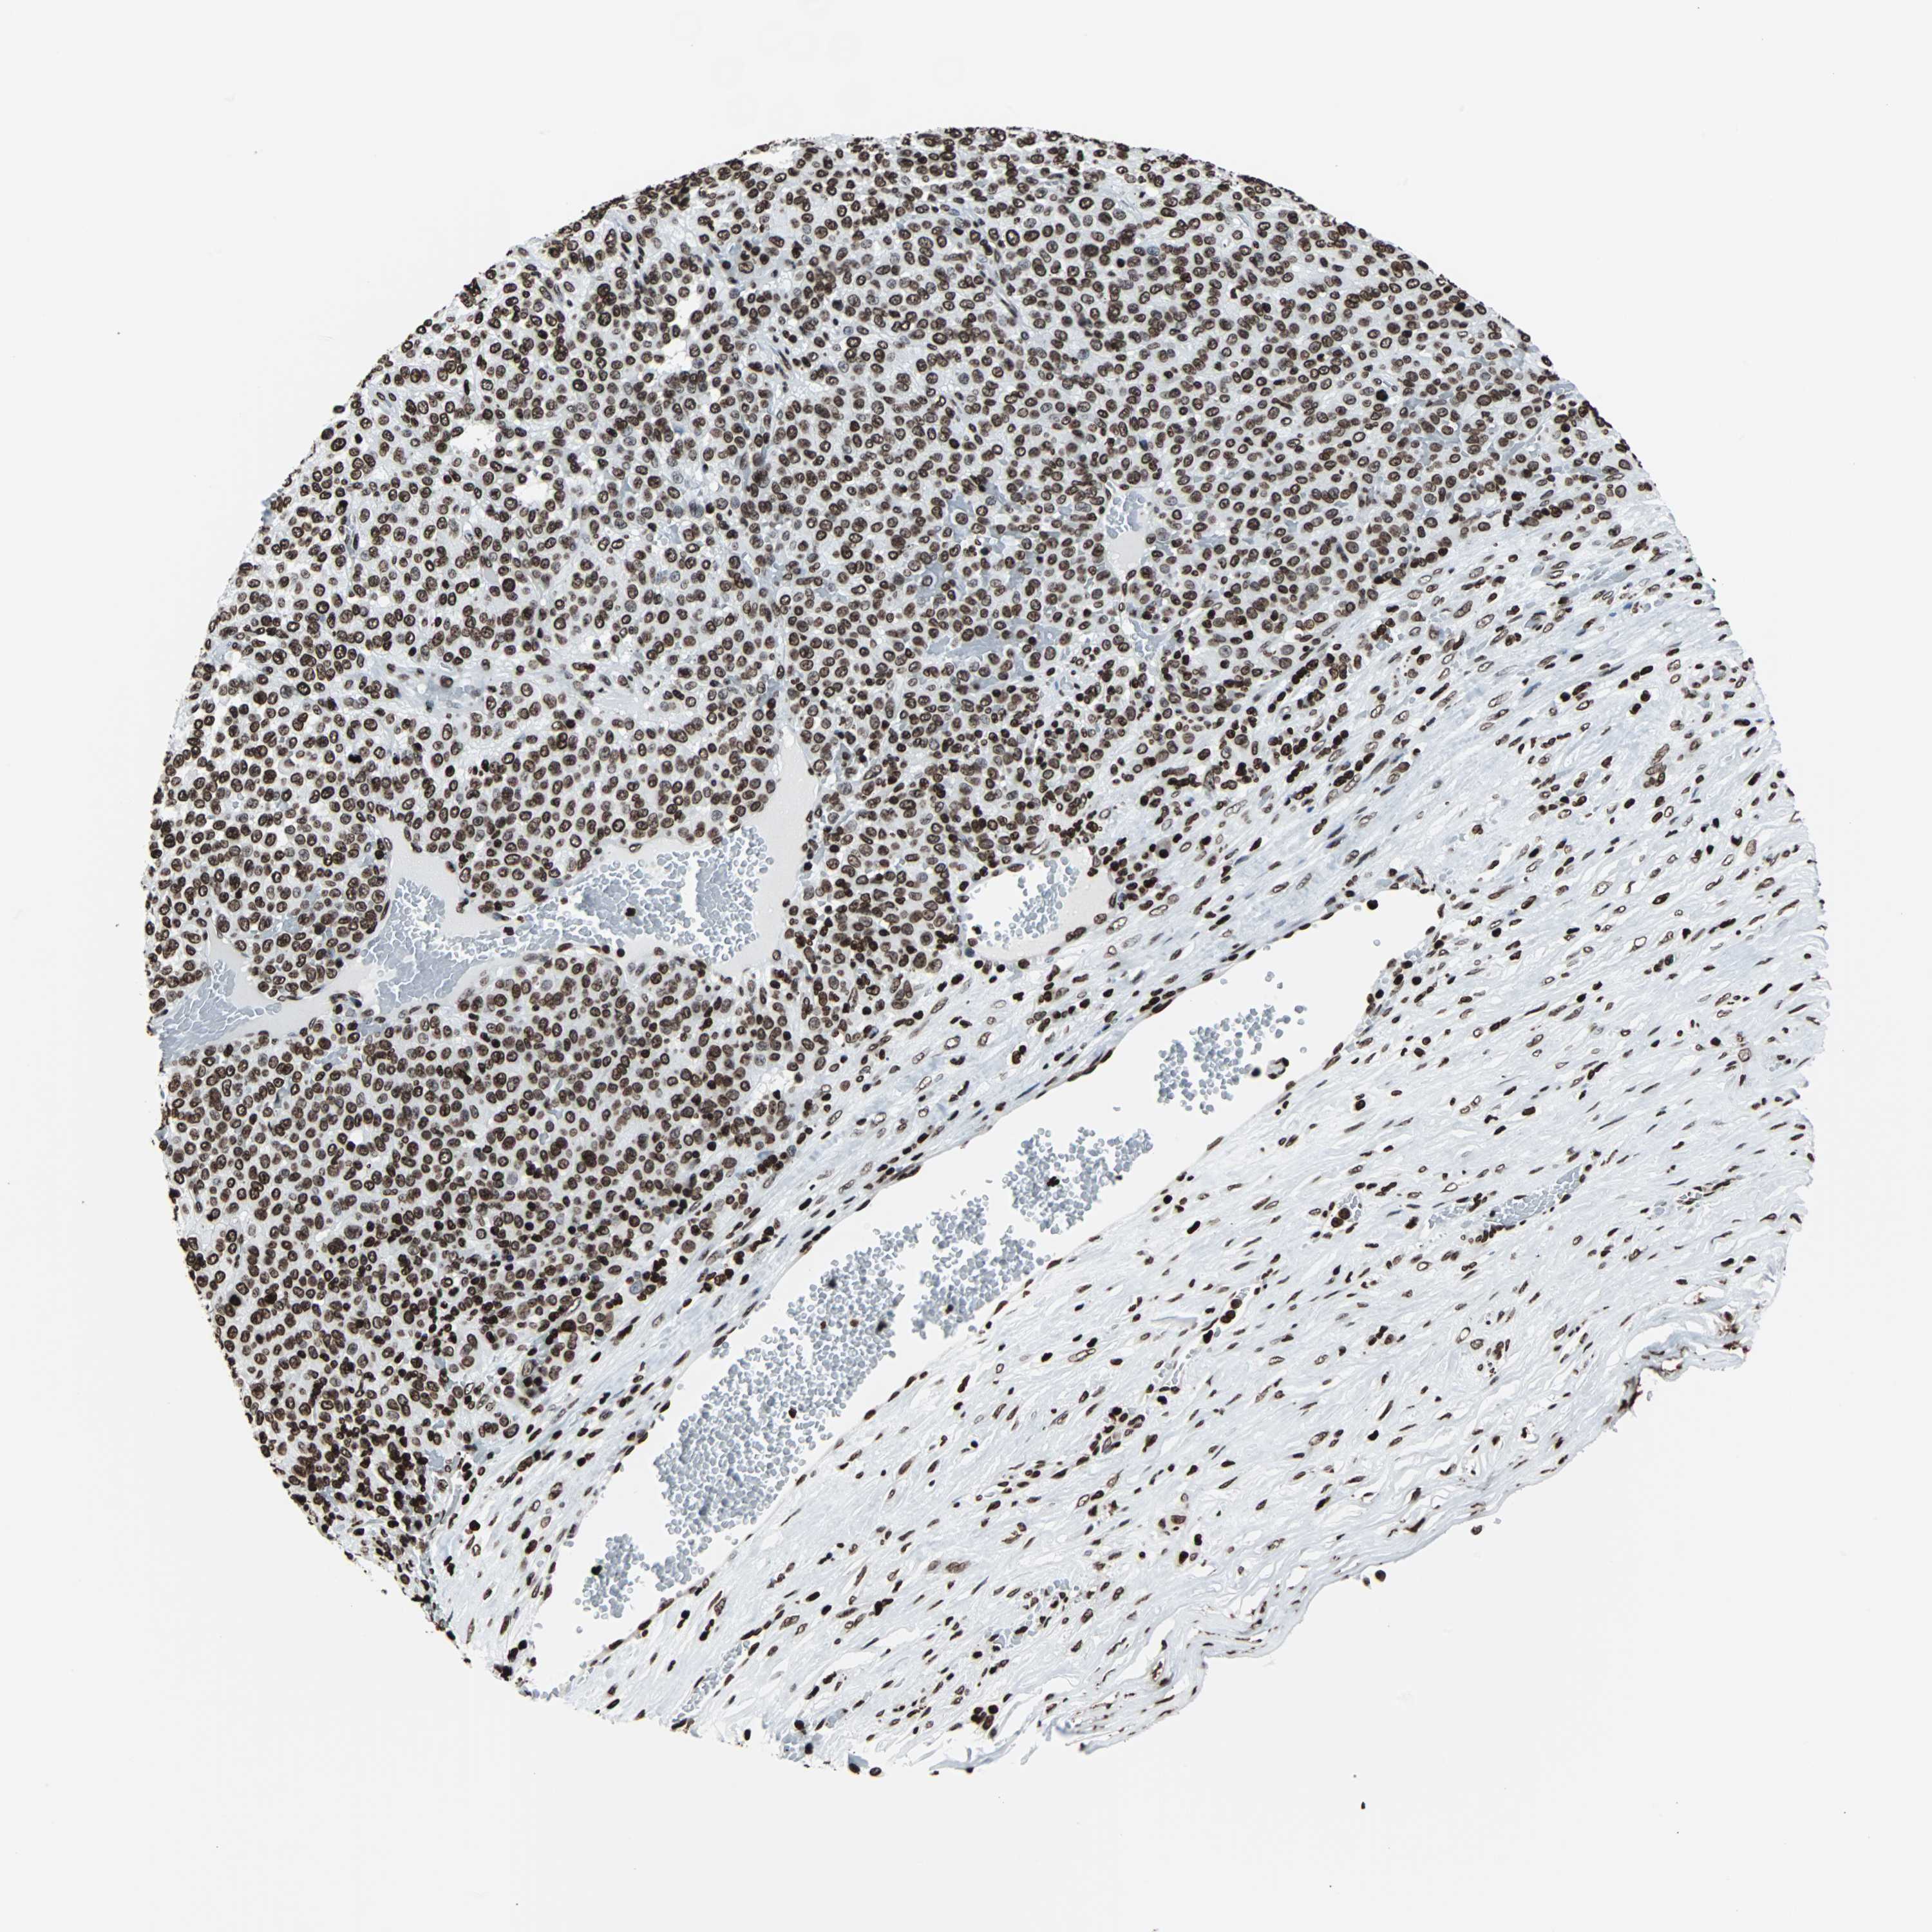

MELANOMA - Protein expressioni

A mouse-over function shows sample information and annotation data. Click on an image to view it in a full screen mode. Samples can be filtered based on level of antibody staining by selecting one or several of the following categories: high, medium, low and not detected. The assay and annotation is described here.

Note that samples used for immunohistochemistry by the Human Protein Atlas do not correspond to samples in the TCGA dataset.

Antibody stainingi

Antibody staining in the annotated cell types in the current human tissue is reported as not detected, low, medium, or high, based on conventional immunohistochemistry profiling in selected tissues. This score is based on the combination of the staining intensity and fraction of stained cells.

Each image is clickable and will lead to virtual microscopy that enables deeper exploration of all samples and also displays staining intensity scores, fraction scores and subcellular localization as well as patient and tissue information for each sample.

Antibody CAB007814

Staining

High

Medium

Low

Not detected

Intensity

Strong

Moderate

Weak

Negative

Quantity

>75%

75%-25%

<25%

None

Location

Nuclear

Cytoplasmic/membranous

Cytoplasmic/membranous,nuclear

Malignant melanoma, Metastatic site